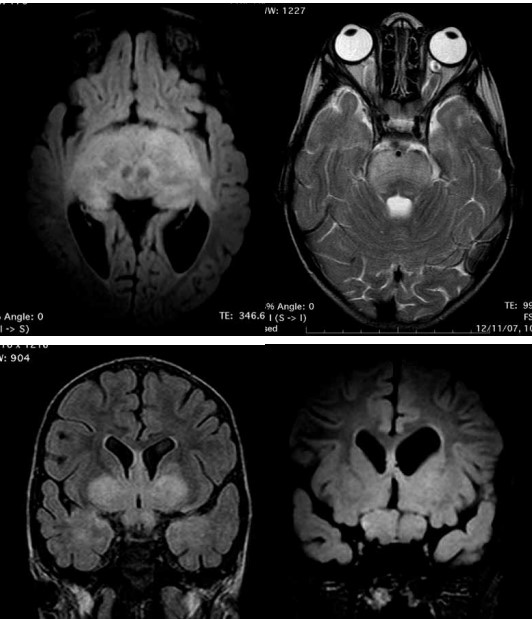

Criança de 03 anos de idade realizou ressonância magnética (RM) de crânio, apresentada a seguir, devido à queixa de cefaleia, associada a alterações visuais e baixa estatura.

(Arquivo pessoal; imagem usada com autorização)